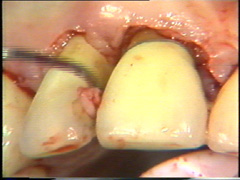

Observese como se

ha eliminado el tejido de granulación en el segundo premolar. |

Eliminación del

tejido de granulación |